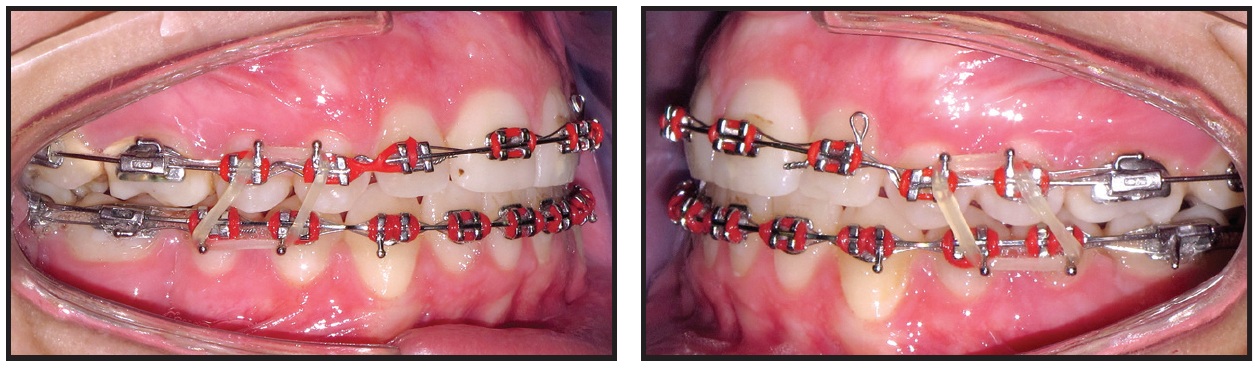

Retraction mechanics were applied to distalize the lower buccal segments and protract the second molars (Fig. 6). Three months later, the lower premolars and canines had been retracted enough to relieve the anterior crowding and allow anterior alignment without proclination (Fig. 7).

Fig. 6 Retraction mechanics applied to distalize lower buccal segments and protract second molars.

Fig. 7 Three months later, lower anterior teeth bonded and space closure initiated in upper arch.

The lower right third molar was surgically exposed and de-impacted with the “MUST” technique, which utilizes nickel titanium leveling archwires and bondable double tubes10 (Fig. 8).

Fig. 8 Surgical exposure of lower right third molar followed by uprighting with “MUST” technique.10

Following two months of molar uprighting, the extraction spaces in both arches were closed in another three months (Fig. 9). The upper first premolars were reshaped by gradual grinding of the palatal cusps to prevent any interference in lateral excursive movements.